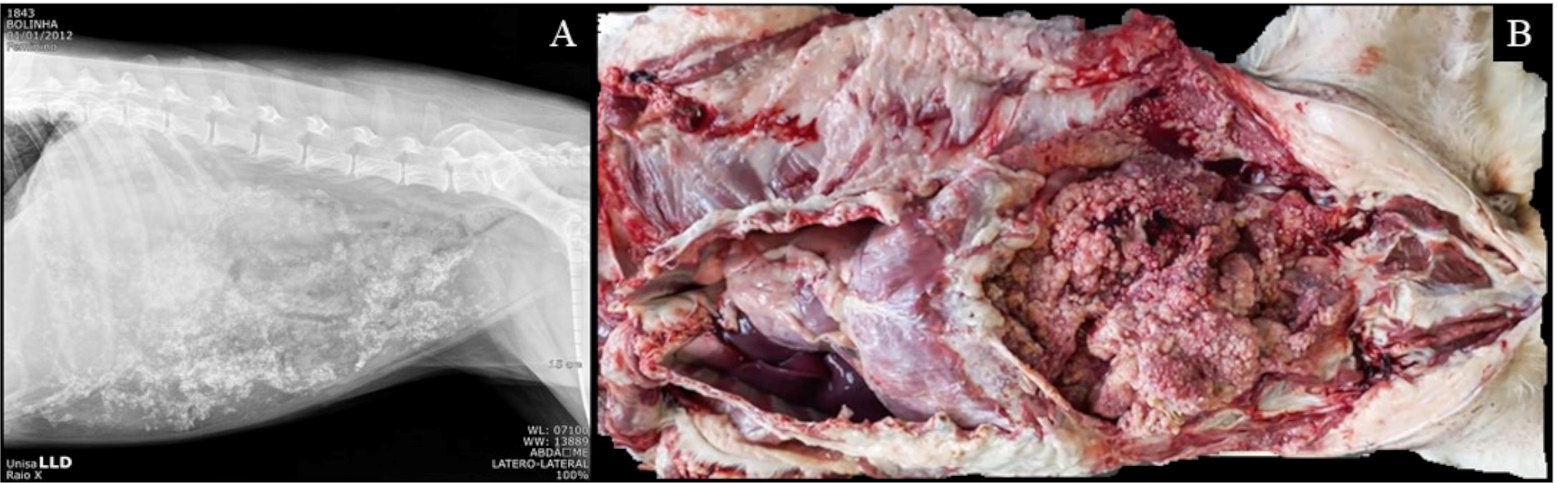

A 10-year-old female mixed-breed dog (Canis Lupus familiaris) presented bulging abdomen with abdominal pain tenderness for 2 weeks and achesia for 1 day, with normochesia, normodipsia, normouria and normophagia. The animal spent most of the time in recumbency, however, it remained alert and responsive. Radiographic examination revealed several amorphous areas of greater radiopacity dispersed throughout the abdominal cavity (mineralizations to clarify, Fig.1A) and the ultrassonografic evaluation showed a presence of hyperechoic areas forming posterior acoustic shadowing dispersed throughout the parenchyma (mineralizations). In this day, 5.5 liters were drained from the abdominal cavity, with a reddish color and cloudy appearance, and 5ml was sended to a cytological analysis, resulting in a modified transudate. This sample had moderate cellularity, composed predominantly of macrophages foamy cells, followed by intact neutrophils, lower quantity of reactive mesothelial cells and small lymphocytes. Presence of microfilariae. A 4DX test was performed, indicating positive for Anaplasma.

Figure. 1. (A) Radiographic examination with several mineralizations dispersed throughout the abdominal cavity. (B) Macroscopy of the irregular, rounded, whitish, firm to hard, solid, multiples structures distributed diffusely throughout the abdominal cavity, liver and intestines.

The dog was treated for recurrent ascites, dilofilariasis and anaplasma for 5 months and an exploratory laparotomy was performed, enabling visualization of multiple nodular areas spread throughout the parietal peritoneum, visceral and ligamentum sickle cell, in addition to intense area of calcification throughout the abdominal parenchyma. During surgery, the animal's condition worsened, and euthanasia was carried out. The body was sent for a necropsy analysis.

Upon the necroscopic evaluation, the animal presented 200 mL of a reddish and clear liquid inside the abdominal cavity (abdominal effusion). In addition to irregular, rounded, whitish, firm to hard, solid, multiples structures distributed diffusely throughout the abdominal cavity, liver and intestines (Fig.1B). The lungs drained a moderate amount of frothy and reddish liquid content. (pulmonary edema). In the right ventricle and pulmonary artery there were cylindrical, whitish parasites, in moderate quantity (dirofilaria).